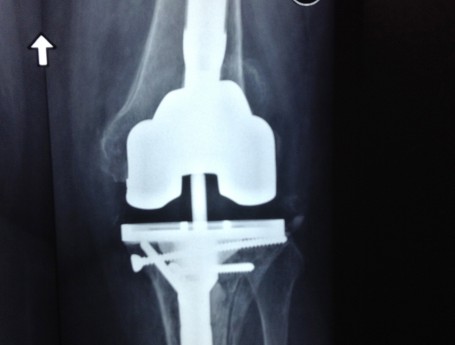

Revision Total Knee Replacement After Infection

• Revision Total Knee Replacement After Infection